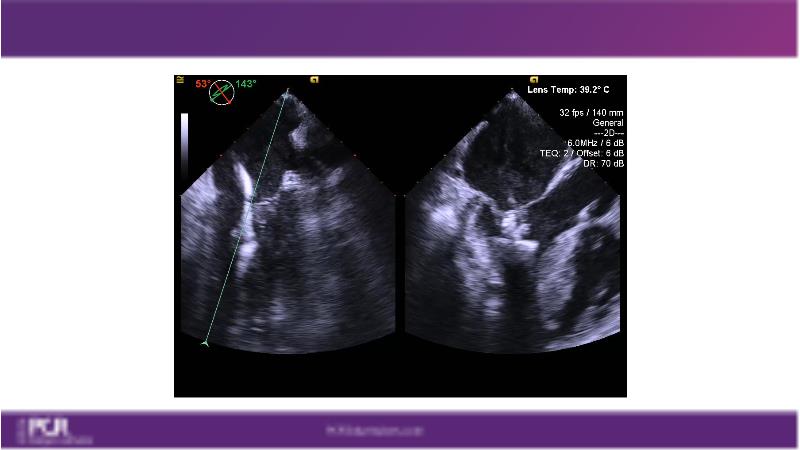

Watch this session to get an overview of a new TEER device, follow the step-by-step procedure related to initial experiences with this device for a Japanese patient with degenerative mitral regurgitation, learn about the latest data from RCT and registries, and follow discussions of challenging TEER cases!

- To learn procedural step-by-step of novel device